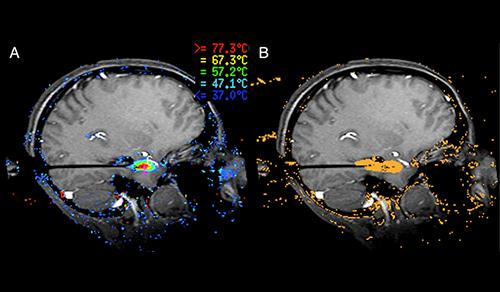

Innovative technologies and alternatives to traditional treatments are transforming the diagnosis and management of neurological conditions. In 2025, NewYork-Presbyterian physicians and surgeons from Columbia and Weill Cornell Medicine used sonication and convection-enhanced delivery to penetrate the blood-brain barrier, validated an adjunctive treatment for subdural hematoma, broadened access to spine surgery, advanced experimental therapies for neurodegenerative diseases, and more. Our specialists have been steadfast in reshaping the fields of neurology and neurosurgery in the pursuit of better patient outcomes and enhanced quality of care.

From cutting-edge research to compassionate patient practice, neurologists and neurosurgeons from Columbia and Weill Cornell Medicine are at the forefront of developing and applying the most advanced approaches to treat debilitating conditions affecting the brain and spine. With a broad range of focus on neurodegenerative and neurovascular disorders to malignant tumors, our innovative and advanced care is leading to new treatment options and enabling patients to achieve the best possible outcomes.